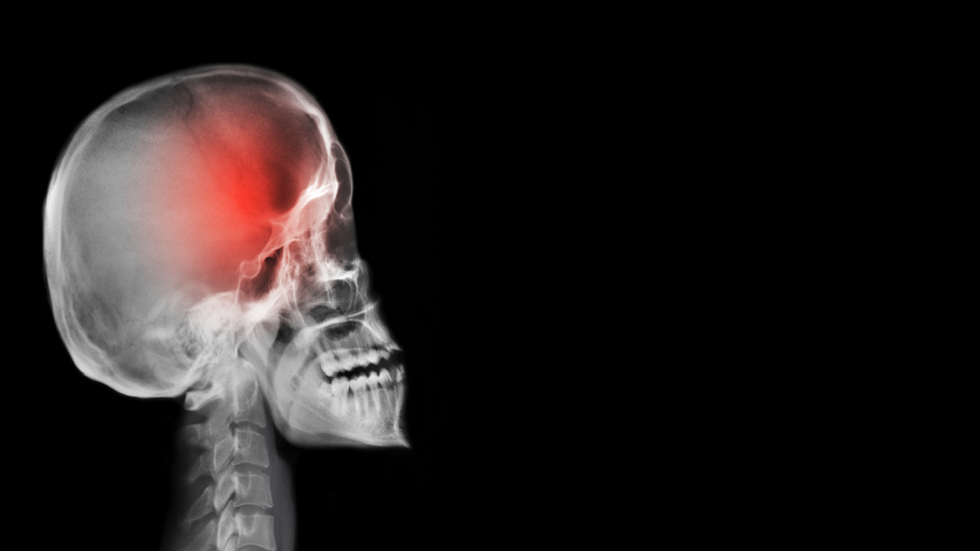

خطأ فادح نرتكبه عند الشعور بالصداع

أعلن الطبيب الروسي ألكسندر يفدوكيموف، أخصائي طب الأعصاب، أن تناول الأدوية عند الشعور بالصداع قد يشكل خطرا مميتا.

ويشير الأخصائي في حديث تلفزيوني، إلى أن مثل هذه الأعراض قد تخفي أمراضا تهدد الحياة.

خمس علامات رئيسية تدل أن الصداع قد يكون علامة على وجود ورم في المخ!

ويقول، "يمكن أن يظهر الصداع في حالات تسبق الجلطة الدماغية، وفي حالة الارتفاع المفاجئ في مستوى ضغط الدم وتمزق الأوعية الدموية. فإذا قرر الشخص تناول الأدوية لكبح الألم، فقد يؤدي ذلك إلى عواقب وخيمة بما فيها الموت".

ويحذر الأخصائي المرضى من الاستخفاف بحالتهم الصحية، لأن تناول الأدوية المسكنة، يمكن أن يكبح الأعراض، في حين يستمر المرض بالتطور.

ويقول، "في هذه الحالة نكون قد فقدنا الوقت المناسب للعلاج".

وينصح يفدوكيموف، عند ظهور ألم حاد غير طبيعي في الرأس لم يسبق أن شعر به الشخص سابقا، بضرورة استشارة الطبيب فورا ، لتجنب العواقب الوخيمة.

ويضيف، بالطبع قد يكون الصداع بسبب الإجهاد المفرط أو الصداع النصفي.